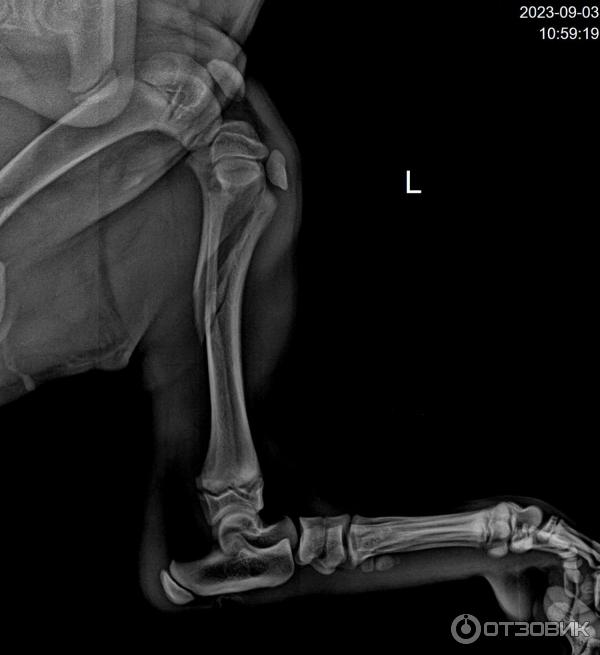

Перелом бедра у собаки

Перелом бедра у собаки 113 фотографий